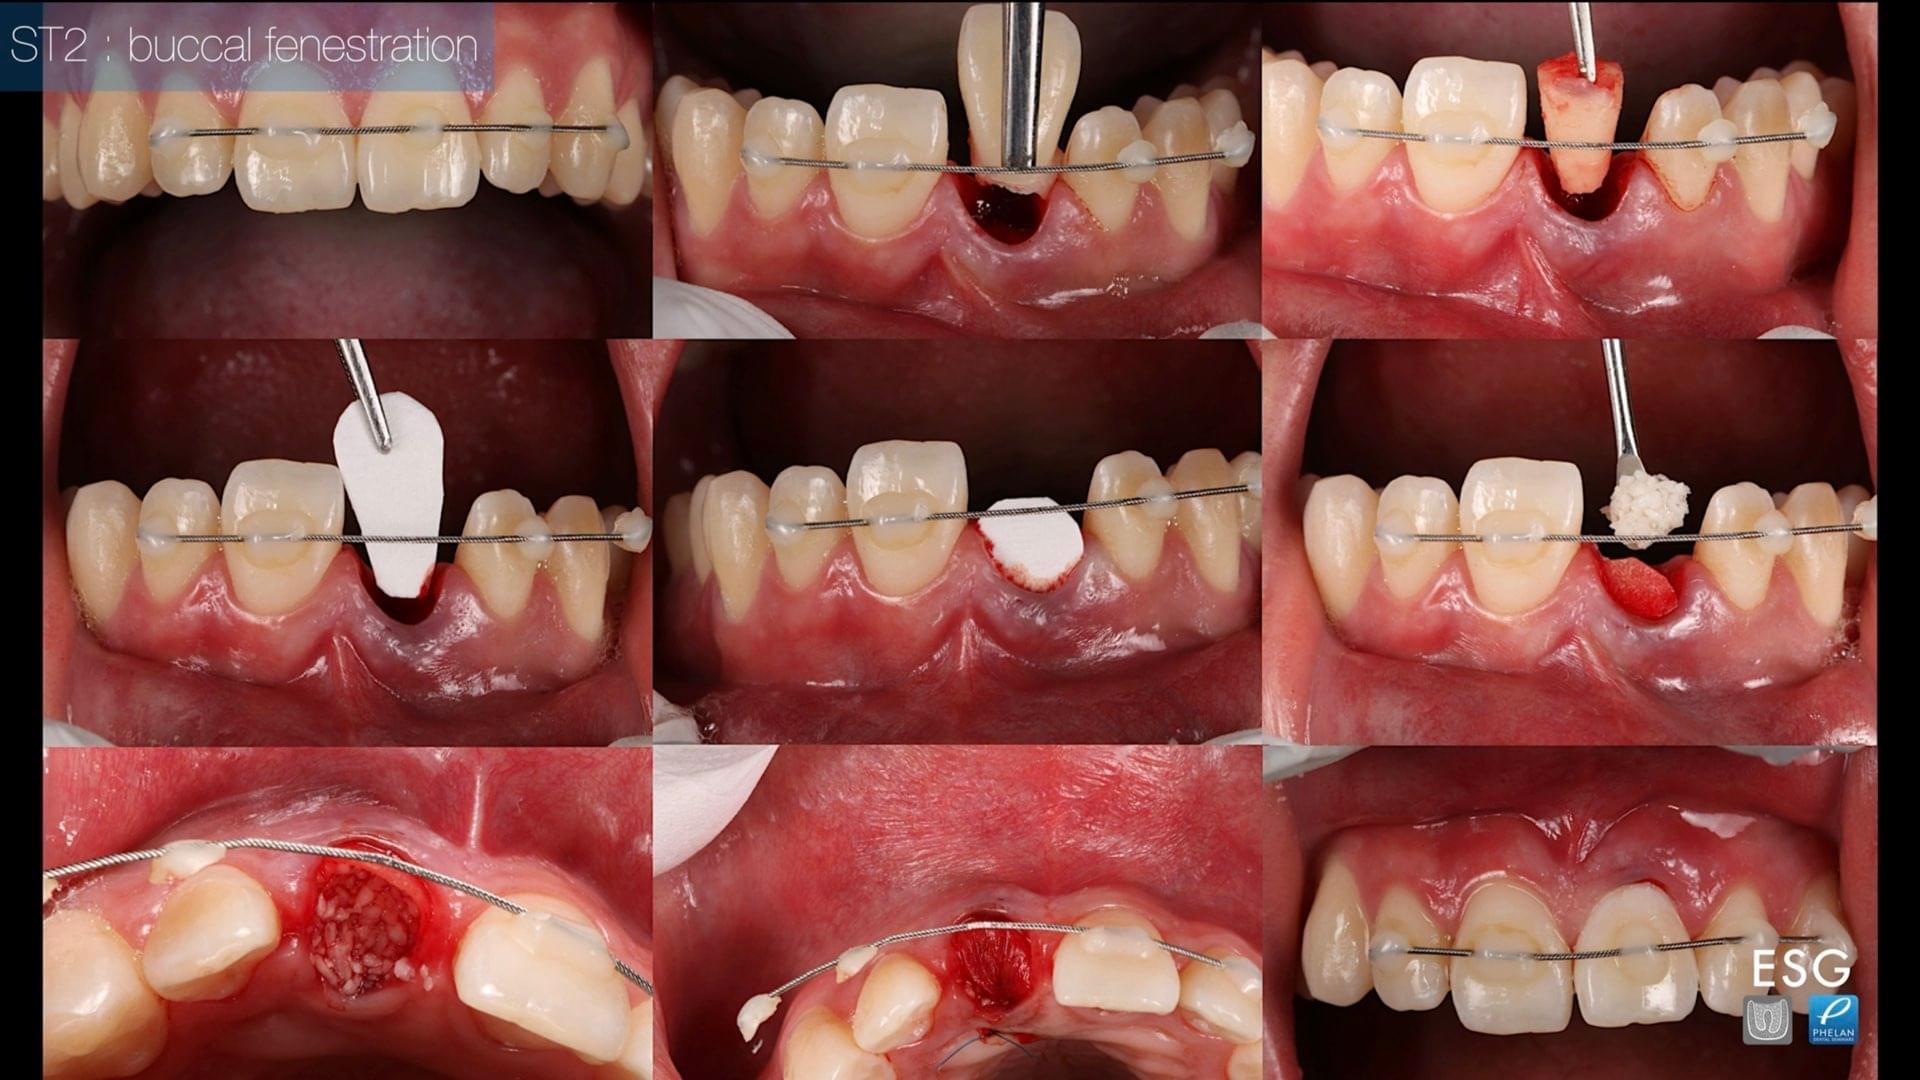

SOFT TISSUE MANAGEMENT IN DENTISTRY- PREDICTABLE SYSTEMS AND TECHNIQUES

Join Dr. Naheed Mohamed and Dr. Stephen Phelan for a free webinar training that will teach you how to be confident and successful with your soft tissue grafting procedures. Learn 6 different types of soft tissue grafts and different harvesting locations and techniques.

This webinar will feature actual cases from Dr. Mohamed’s specialty practice. The presentation will focus on a systematic approach to treatment planning and executing a successful soft tissue grafting procedure.